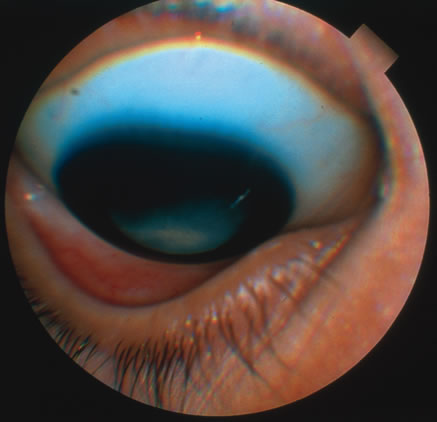

In primary ocular HSV infections, a severe follicular conjunctivitis with regional adenopathy is present. Vesicles may appear on the eyelid skin or lid margin, producing blepharitis (Fig. 3). Corneal involvement initially takes the form of a superficial punctate keratitis, which may progress to dendritic or geographic ulceration. Stromal infiltrates and uveitis are less common and relatively mild in primary disease. In uncomplicated cases, lesions usually heal completely in 2 to 3 weeks without scarring. Most cases of ocular HSV are recurrences. Recrudescent ocular herpes may take the form of dendritic or geographic ulcers, recurrent erosions, interstitial or disciform stromal keratitis, and anterior uveitis.3 HSV may also be an agent of retinitis and acute retinal necrosis (Fig. 4).